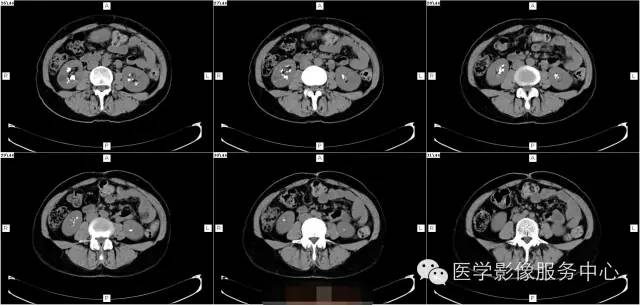

病史:

女,37岁,血尿一周

髓质海绵肾(简称MSK)又称Cacchi Ricci disease,是一种先天发育性肾髓质囊性病变,发生率约1:2000-5000,多见于40-60岁男年,70%为双侧肾脏发病,病变局限于髓质范围内,常累及两侧肾的多数锥体和乳头,形成许多数毫米的囊腔使髓质如海绵状,故名海绵肾,病理特点为集合管远端扩张,形成圆形或不规则型囊腔,囊内壁衬以立方或扁平上皮,囊内充溢脱离的上皮及钙化形成的小结石。

1、腹部平片表现肾影正常或稍增大,两侧或单侧肾实质内多发圆形、类圆形或不规则形结石,直径2-5MM,呈簇状或扇形分布,有时平片可表现阴性。

2、静脉肾盂造影表现肾脏大小正常或轻度增大,造影剂在肾乳头或扩张集合管呈放射条纹状、花束状,肾功能一般正常。

3、CT平扫表现一个或多个肾锥体内散在或蔟团状多发结石,呈花瓣样或扇形分布;部分腹部平片阴性,CT平扫可发现肾锥体内细小的结石。增强扫描表现扩张的肾集合管内有条纹状、刷状、小囊状或扇形的造影剂浓聚。部分患者肾实质内可见多发小囊肿。